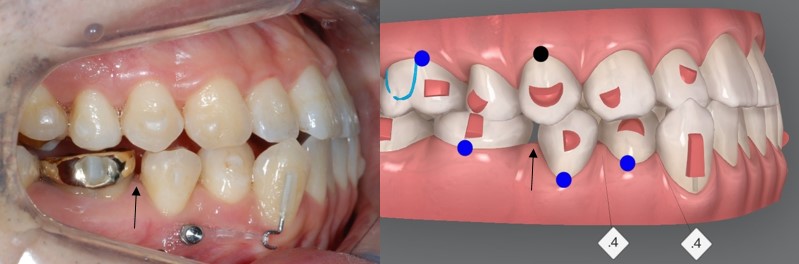

교정을 시작한지

6개월이 지나

중간점검차

사진을 찍어보았는데요

오른쪽 사진의 틈 보이시나요?

틈!!

어금니 사이에 공간이 생겼어요!!

남편은 비발치 인비절라인 교정으로,

우측 아래 치아 전체를

뒤로 미는 교정을 하고 있습니다.

큰 어금니들이 먼저 뒤로 밀리면서

저렇게 틈이 생기고

저 틈을 이용해 앞니들 또한

뒤로 미는 방법입니다.

인비절라인 클린체크 25번

오른쪽 사진은

46단계중 25단계에

해당되는

인비절라인 클린체크 사진인데요

클린체크의

예상대로

치아의 이동이

잘 되고 있습니다!!!

윗니들도

악궁이 확장되면서

더욱 더 가지런해진 모습을

확인 해 보실 수 있습니다!!